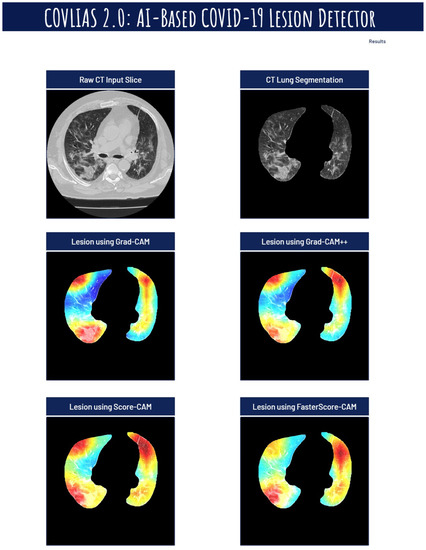

Visual Results Representing Lesion Using the Four CAM Techniques

4.4. A Special Note on Four CAM Models